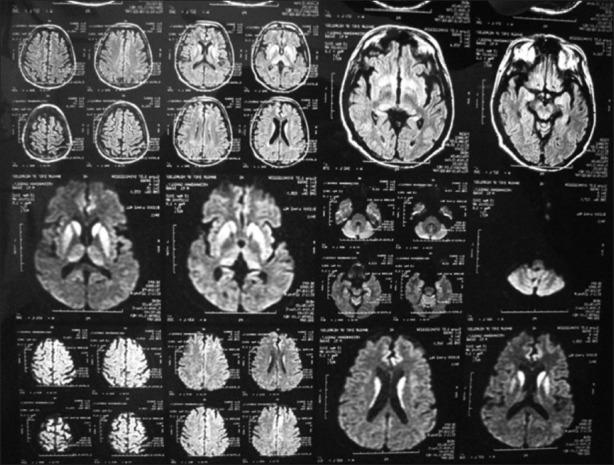

Patients of rapidly developing dementia fulfilling the diagnostic criteria for sCJD were included. All were investigated in detail to find out any possible treatable cause including electroencephalography (EEG), magnetic resonance imaging (MRI) of brain, and cerebrospinal fluid analysis.

A total 10 patients of probable sCJD diagnosed using the European diagnostic criterion between December 2011 and January 2013. The clinical features are consistent with other reported series. While 60% of patients had the classical EEG findings, 100% had typical MRI features. Eight patients died within a mean duration of 4.56 months from the disease onset.

纳入符合sCJD诊断标准的快速发展型痴呆患者。对所有患者进行详细检查,以找出任何可能的可治疗病因,包括脑电图(EEG)、脑部磁共振成像(MRI)和脑脊液分析。

2011年12月至2013年1月期间,共有10例可能患有sCJD的患者根据欧洲诊断标准被确诊。临床特征与其他报告系列一致。60%的患者有典型的脑电图表现,100%有典型的MRI特征。8例患者在疾病发作后的平均4.56个月内死亡。